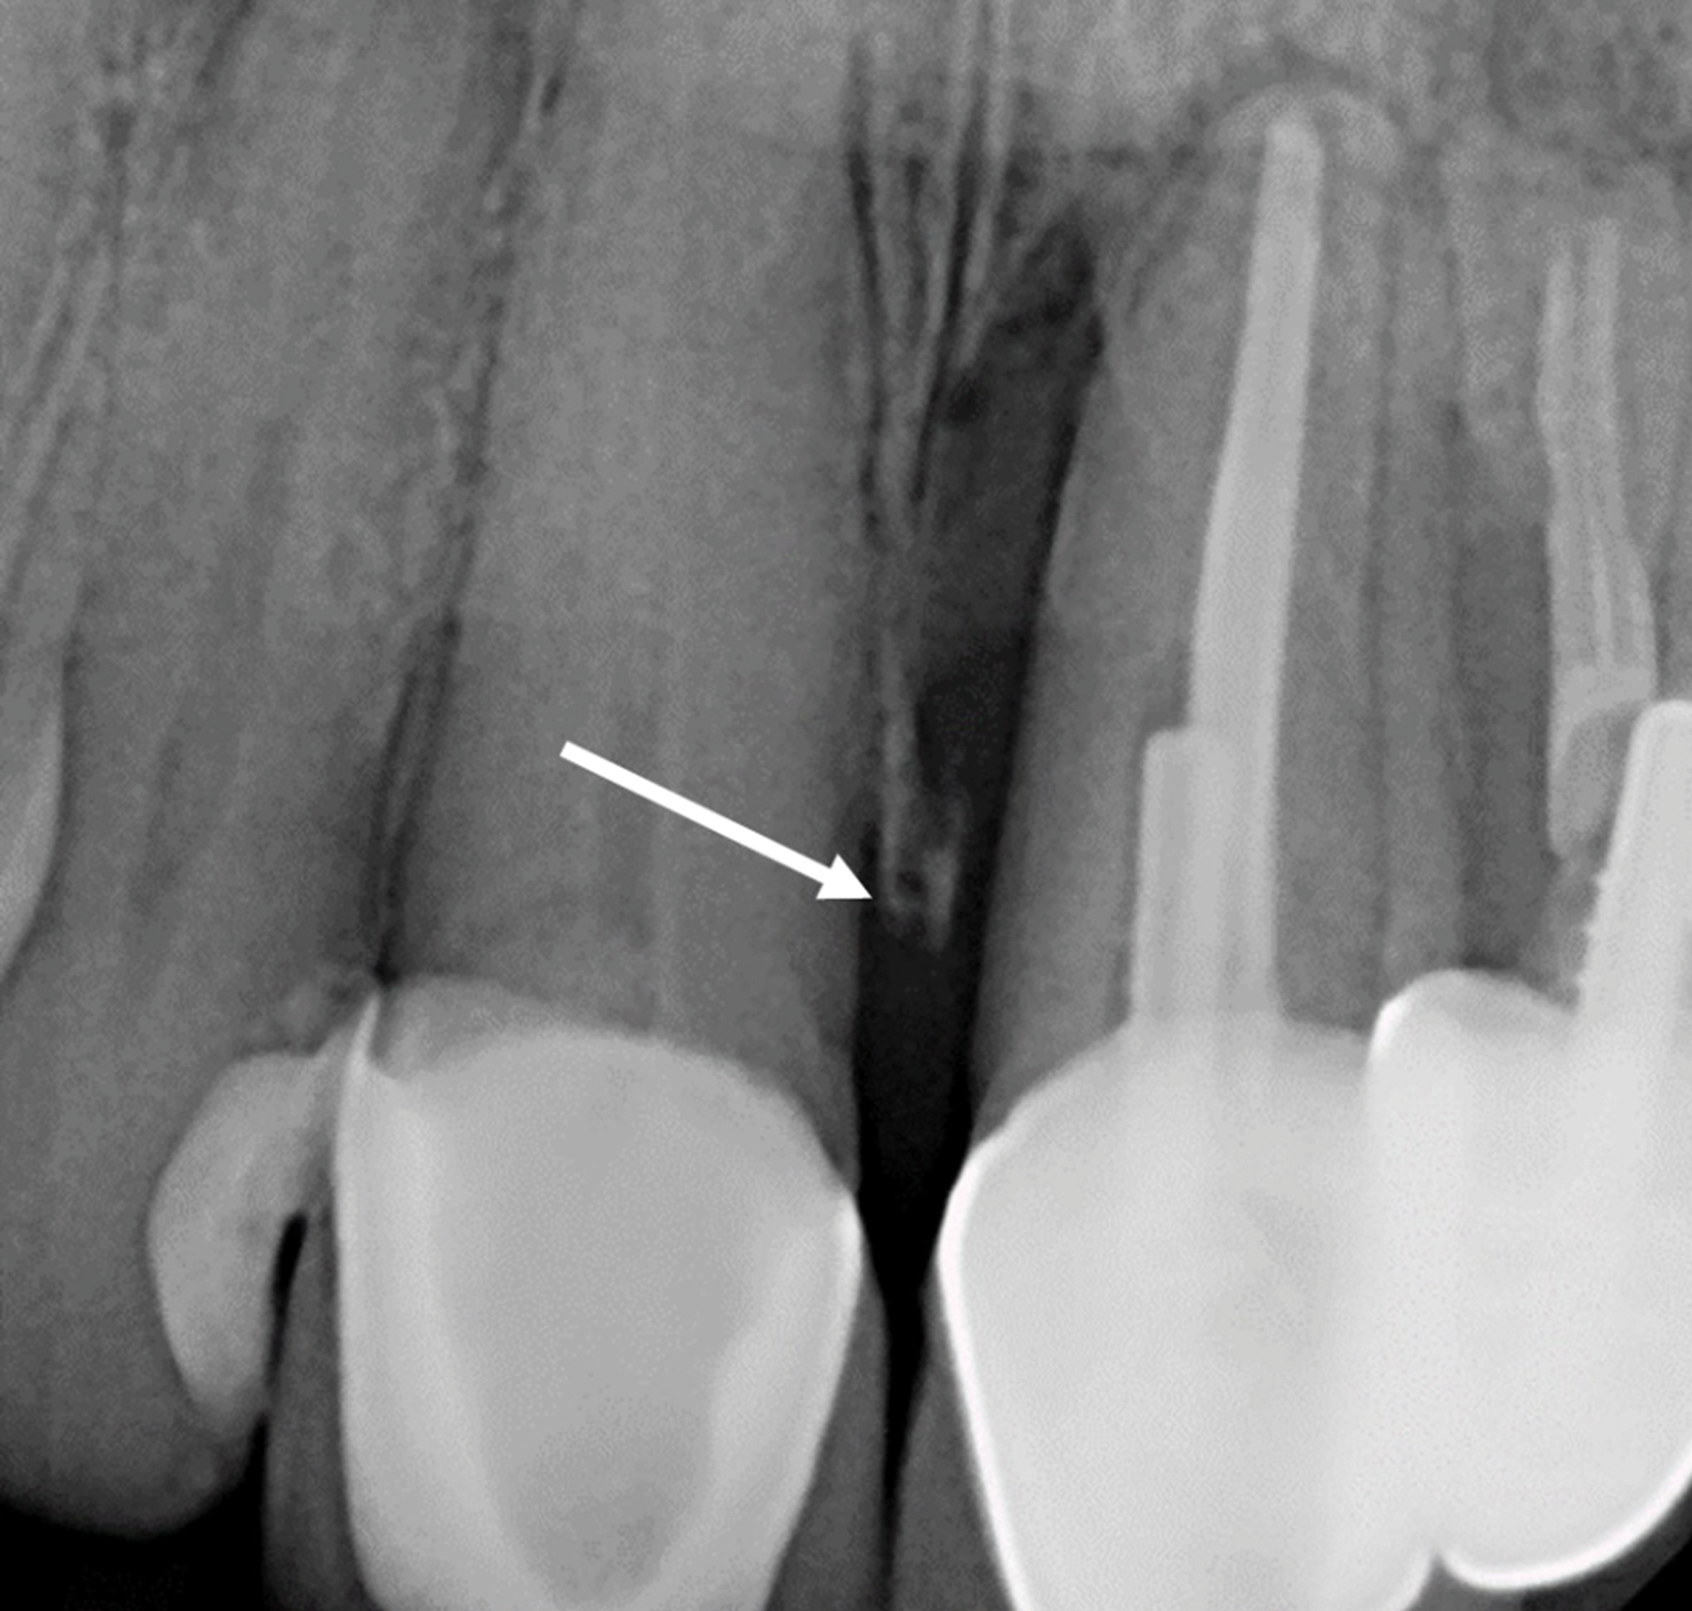

After an extraction, subsequent papillary height is dictated by the interproximal bone height on teeth adjacent to the extraction site. It is the supercrestal fibers on contiguous teeth that maintain papillary height adjacent to the extracted site.8 If the osseous crest is <5 mm from the contact area, the papilla will reform; if it is >5 mm, regeneration is unpredictable and probably only 50% of the papilla will regenerate.8 Grunder also demonstrated that papillary height depends on the bone level of the tooth side, not the implant side, of an interdental area (Figure 4).11 Hereported that papillae height adjacent to extraction sites was 4.23 mm when an implant was placed.11 Note that a hopeless tooth should not be considered a useless tooth, because it can be orthodontically extruded and used to help restore ridge anatomy.12

Fig 4. Radiograph of teeth Nos. 8 and 9. After tooth No. 9 is extracted, the height of the papilla will depend on the height of the bone on the mesial side of tooth No. 8, not the implant side of an interdental area. The arrow indicates the mesial osseous crest on tooth No. 8.

Figure 4